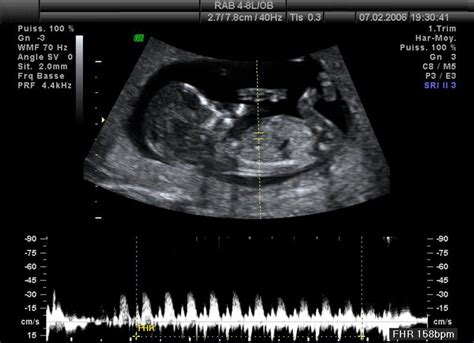

- Srdiečko dieťatka začne pumpovať asi v 6. týždni. To znamená, že pri ultrazvukovom vyšetrení v 8. týždni si môžete vypočuť zvuky jeho pumpovania. Bije rýchlosťou asi 160 tepov za minútu. Je to úžasný zážitok!

Detská pokožka je ružová, chĺpky (lanugo) sa začínajú strácať, obvod hlávky sa oproti 32. týždňu zväčšil o ďalší centimeter a srdiečko bije rýchlosťou 120 až 160 úderov za minútu. Drobček sa vie smiať, mračiť i plakať. Bábätko je takmer úplne vyvinuté, musí však ešte podrásť. Váži približne 2 kg a meria 44 cm.